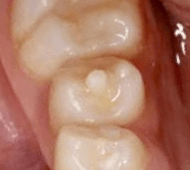

「中心結節」生え変わった臼歯の〝小さな突起〟見逃せない悪影響とは

デンタルケア

子どもの健康

筆者撮影